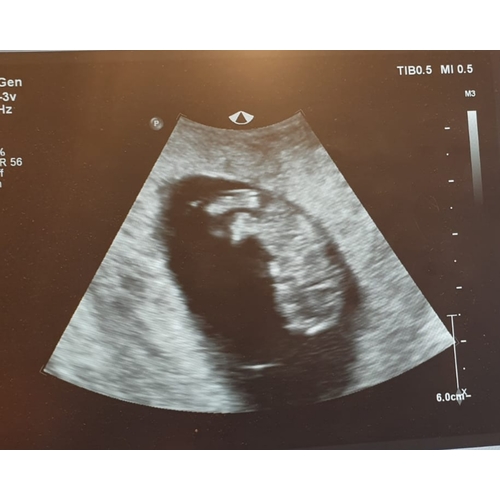

Het kan ook een meetafwijking zijn. Zo vroeg in de zwangerschap geeft 1 mm fout gemeten al een paar dagen verschil. De hoek van de echo is daarbij ook heel belangrijk. Anders kan iets op de echo kleiner lijken dan het is.

Maar ik geloof niet dat het op een miskraam eindigd, want hartje klopte zo intens goed

Ik denk dat het niks is om je zorgen om te maken!! Ik dacht zelf 28 juni uitgerekend te zijn. Bij de echo met 7 en 'n halve week ben ik 1 dag terug gezet, met de echo van 9 weken weer 3 dagen terug gezet (dus 3 in totaal) en nu bij de 12 weken echo heeft de baby 4 dagen groei ingehaald!! Ik ben dus!"al" 27 juni uitgerekend. Het is gewoon echt mm werk.. En wie weet is ie dalijk bij de volgende echo een heel eind gegroeid ☺️

Een afwijking van 2 dagen tussen 2 echos in is niet veel. En alle dateringsecho's hebben een foutmarge. Op mijn echo rapporten staat: +- 4 dagen. Dus dat geeft wel aan dat 2 dagen niet zo veel is en binnen de te verwachtte foutmarge valt.